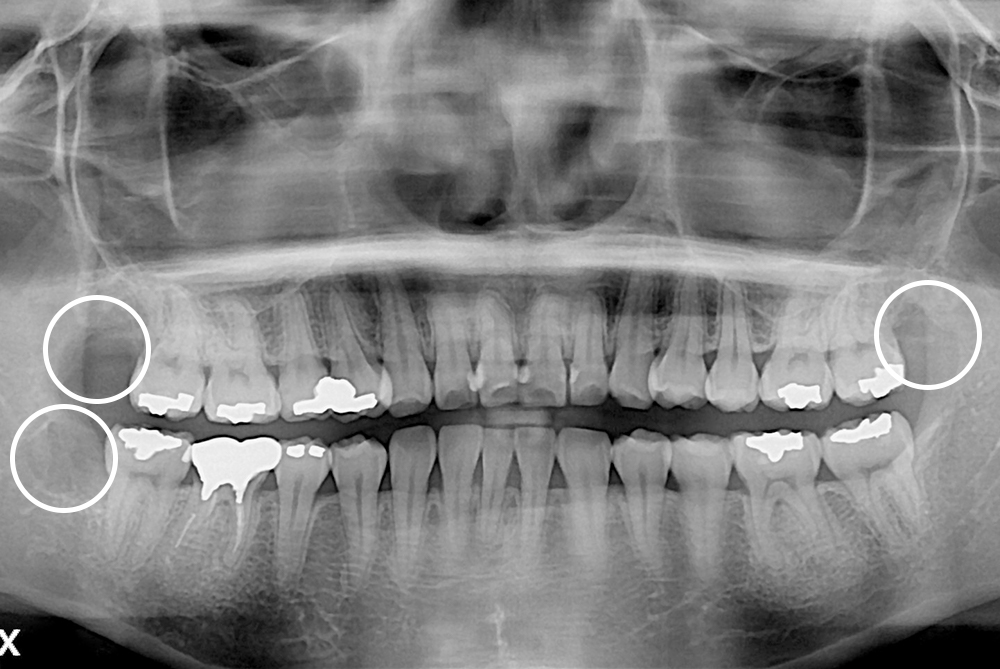

[사랑니] 매복 사랑니 발치

치료후 : 2020-01-31

세종치과는 구강악안면외과학 박사이신 원장님이 발치하는 치과입니다.